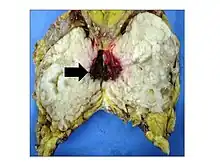

Gross image of an excised phyllodes tumor.

Malignant phyllodes tumors can behave similarly to sarcomas leading to development of blood-borne metastases.[16] Approximately 10% of phyllodes tumor develop distant metastases and this occurrence is higher (20%) in patients with histological-identified malignant tumors.[16] The most common site for distant metastases include the lung, bone, and abdominal viscera.[17] In more insidious cases, the parotid region has also been described in literature.[18]